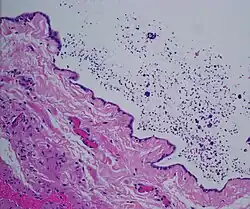

| Ultrasound of a testicle (grey) and a spermatocele (black). | |

Spermatocele is a fluid-filled cyst that develops in the epididymis.[3] The fluid is usually a clear or milky white color and may contain sperm.[4] Spermatoceles are typically filled with spermatozoa[5] and they can vary in size from several millimeters to many centimeters. Small spermatoceles are relatively common, occurring in an estimated 30 percent of males.[6] They are generally not painful. However, some people may experience discomfort such as a dull pain in the scrotum from larger spermatoceles.[7] They are not cancerous, nor do they cause an increased risk of testicular cancer. Additionally, unlike varicoceles, they do not reduce fertility.[7]

Spermatoceles can originate as diverticulum from the tubules found in the head of the epididymis. Sperm accumulation gradually causes the diverticulum to increase in size, causing a spermatocele. While there are many tubules connecting the epididymis to the testis, a blockage in one of the tubules may lead to formation of a cyst.[18] In many instances they appear to occur spontaneously without any preceding instances of injury.[6]

The primary care physician may diagnose and manage benign causes of scrotal masses such as hydrocele, varicocele and spermatocele. However, if a "must not miss" diagnosis related to testicular masses such as testicular torsion, epididymitis, acute orchitis, strangulated hernia and testicular cancer is suspected, the family physician must refer to a urologist.[19] Finding a painless, cystic mass at the head of the epididymis that is clearly separate from the testicle can indicate a spermatocele. Shining a light through the mass, a process known as transillumination, can also help differentiate between a fluid-filled cyst and a tumor, which would not allow as much light to pass.[20] If uncertainty exists, ultrasonography of the scrotum can confirm the presence of a spermatocele.[7] The location and history of any scrotal masses are crucial in determining whether or not the mass is benign or malignant.[21] Lab tests such as a complete blood count (CBC test) or urine test can also be conducted to check for any possible infection or signs of inflammation.[22]